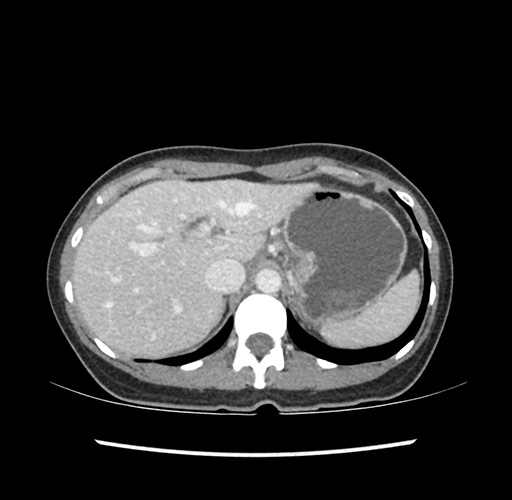

Left lateral sectionectomy [case 12]

Imaging Analysis

Look through the patient's CT scan to identify any areas of concern for the necessary procedure.

Based on your CT findings, which issue(s) would give reason for "planned slowing down moment(s)" in this case?

Considering a standard left lateral sectionectomy procedure, what step(s) of the operation would you do differently in this case ?